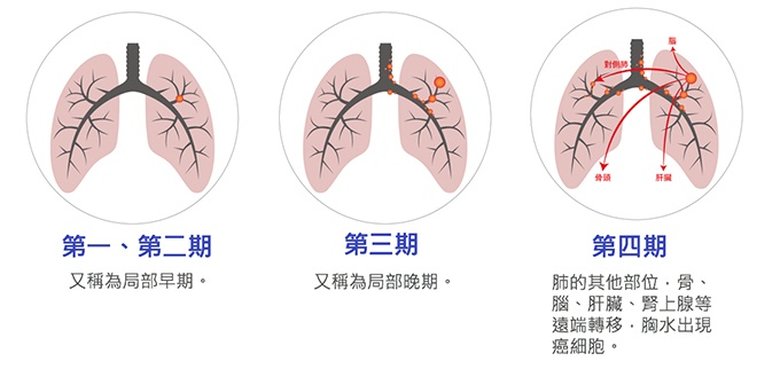

統計顯示,30年來,台灣肺癌的發生率增加了3倍,更可怕的是發生率還在繼續上升。而國健署的癌症統計顯示,國人被診斷出罹患肺癌時有6成左右是已經轉移,無法手術治癒的晚期(第4期)癌。在台灣,剛診斷出肺癌的平均年齡是65歲,但是從55歲開始發生率就有快速升高的趨勢。

目前對肺癌的分類從原本單純的病理分類,還有新1種的「分子分類」出現。病理分類就是從病理切片依據細胞型態排列的方式所做出的分類,可粗分為小細胞肺癌和非小細胞肺癌兩種,前者占所有肺癌的10%至15%,後者則占85%至90%;同時,非小細胞肺癌又分為肺腺癌和鱗狀細胞肺癌兩種,以及極少數幾乎消失可以不計的大細胞肺癌。

此外,隨著肺癌的治療日益複雜,肺癌的分類方式也慢慢朝向所謂的「分子分類」,尤其以肺腺癌為甚。這是因為肺腺癌的癌細胞往往具有EGFR、ALK、ROS1 等十餘種的其中1種的(肺癌驅動)基因突變,藉由基因檢測出可以得知病友具有哪一種基因的突變,能夠藉此進行標靶治療。另外,利用特殊染色評估癌細胞或免疫細胞之免疫檢查點PD-L1 表現,可作為能否進行免疫治療的依據。這也是分子分類的1種方式。經過完整的檢查後,才能正確判斷期別,也才能制定正確的治療計畫。